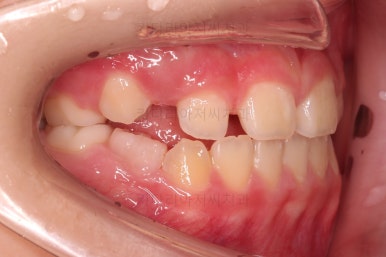

초진 시 입안의 모습입니다.

아래쪽 치열이 전반적으로 윗니보다 앞쪽에 위치한 전형적인 앵글씨 3급 부정교합인데요.

어금니에서부터 앞니까지 아랫니가 윗니보다 앞쪽에 위치하네요.

특히 앞니는 아랫니가 윗니보다 나와있는 "반대교합" 상태였고요.

또한 위아래로 겹침이 없고 떠있는 "개방교합" 상태였어요.

즉, 앵글씨 3급 부정교합 - 반대교합 - 개방교합 등 굉장히 복합적인 교합의 문제를 가진 환자였습니다.